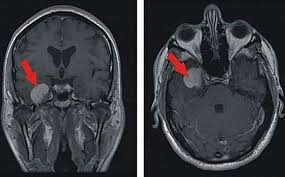

Klinik Und Poliklinik Fuer Neurochirurgie Meningeome